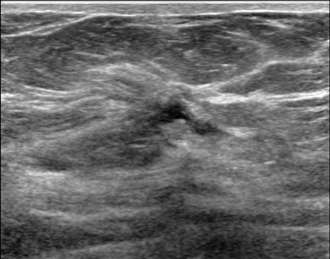

Sonographic architectural distortion

The ultrasound image above demonstrates sonographic architectural distortion. The hyperechoic (bright) bands of tissue interdigitating between the fat in the breast become focally altered and seem to radiate around a small lesion. Biopsy revealed a complex sclerosing lesion (sometimes called a radial scar) which is a benign, but sometimes high risk lesion, which can be recognized as architectural distortion on ultrasound. Other examples of benign causes of architectural distortion include sclerosing adenosis, fat necrosis, post-procedural changes, granular cell tumors, and breast fibromatosis. Architectural distortion may also be associated with breast cancer, as evidenced by the example below: